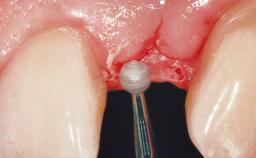

Immediate Flapless Placement of an Implant in a Maxillary Left Central Incisor Site

A 42-year-old female patient was referred to our clinic at the School of Dentistry of the University of São Paulo in November 2004, presenting a deficient restoration in the upper left central incisor. The clinical examination revealed no gingival retraction or any signs of gingival inflammation and, therefore, previous periodontal treatment was not considered. The patient presented a high lip line at full smile and a thin tissue biotype. This combination characterized a high-risk situation from an anatomic point of view, which required careful preoperative planning and cautious surgical execution.

| Loading Protocol | Immediate |

| Provisional Implant-Supported Prosthesis | Prosthodontic margin < 3 mm apical to mucosal margin Prosthodontic margin < 3 mm apical to mucosal margin |